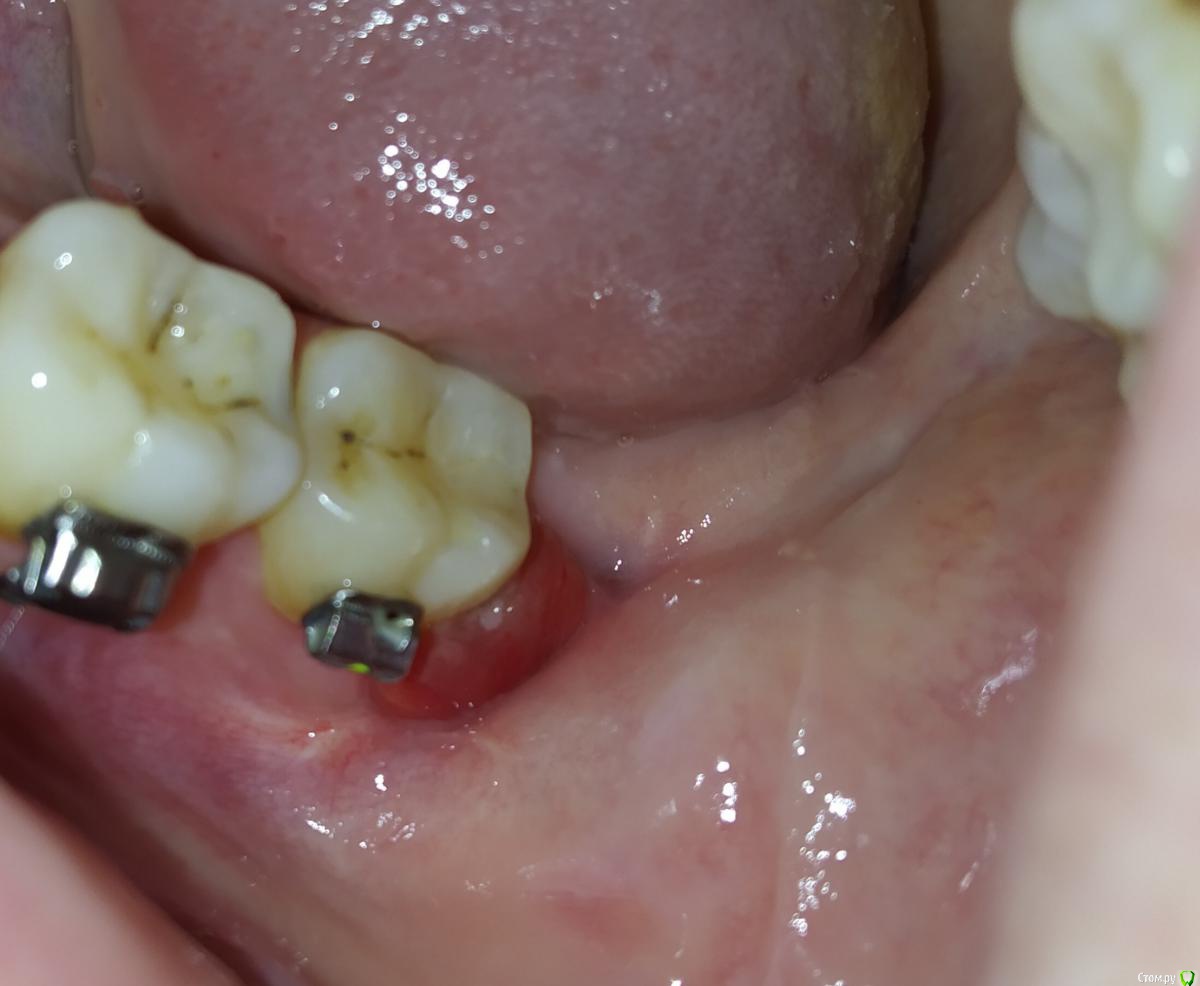

Anastasiamuur Опубликовано 17 мая, 2019 Поделиться Опубликовано 17 мая, 2019 (изменено) 2.04.19 удалили ретинированный зуб мудрости ,28.04 ставили брекеты на НЧ, ортодонт сказал ,что у меня кровит в месте удаления ,я пошла к стоматологу .сделали снимки ,сказали ,что а лунке все хорошо заживает .НО десна в месте удаление красная ,опухшая .Со временем она стала багрово-красной. Кровит ,даже когда дотрагиваюсь щеткой до нее. Ванночки хлоргексидина и Метрогил дента не помогают .отек стал больше за последние 2 недели Изменено 17 мая, 2019 пользователем Anastasiamuur Ссылка на комментарий

kramer Опубликовано 17 мая, 2019 Поделиться Опубликовано 17 мая, 2019 Делали снимок ,сказали ,сто в лунке все отлично ,затягивается ,осколков нет и других посторонних предметов ,альвеолита и ТД тоже нетСнимок показывает только состояние кости и зубов. Вялотекущий воспалительный процесс мягких тканей не будет виден (кстати покажите снимок). Надо сделать кюретаж лунки. Ссылка на комментарий